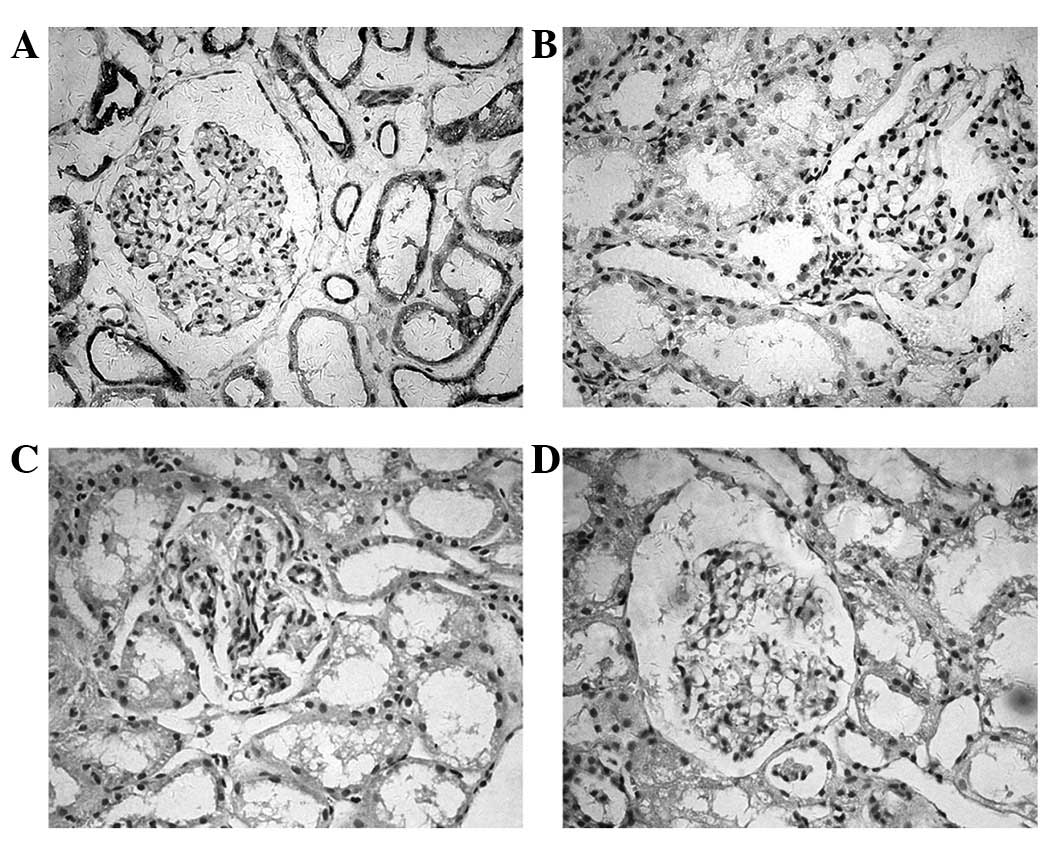

The expression of PD-L1 and PD-L2 in the human renal

biopsy tissue samples was detected by immunohistochemistry. As

shown in Fig. 4, a significant

PD-L1 expression was detected in the tubular epithelium. Positive

staining was detected in the cell membrane or cytoplasm or in the

two together. However, the expression of PD-L1 was not observed in

the glomeruli. Patients with MsPGN were identified as having

increased PD-L1 (P=0.012) expression in the renal biopsy tissues

compared with normal individuals. The intensity levels of the PD-L1

expression in the normal or diseased renal tissues are shown in

Table II. The expression of PD-L2

was not observed in the renal tissues of the MsPGN patients or the

controls.

PD-L1 staining in the renal tubules using immunohistochemistry in

diseased kidneys suffering IgA nephropathy, interstitial nephritis

or lupus nephritis (19). In the

present study, the high expression of PD-L1 was also detected in

the tubular epithelium in the renal biopsy tissues from the MsPGN

patients, suggesting that PD-L1 expression is upregulated in

vivo in inflammatory kidneys. However, the expression of PD-L2

was not observed in the kidneys from the MsPGN patients. The